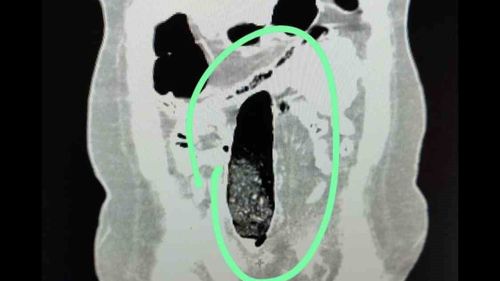

Muş Emniyeti, şehirler arası otobüste yakaladığı 2 İran uyruklu şahsın vücutlarında metamfetamin ve sentetik hap ele geçirildi; iki kişi tutuklandı.

Muş'ta Otobüste Uyuşturucu Sevkiyatına Polis EngeliNarkotik ekiplerinin takibiyle 2 kişi tutuklandıMuş İl Emniyet Müdürlüğü Narkotik Suçlarla Mücadele Şube Müdürlüğü ekipleri, il genelinde yürüttükleri teknik ve analiz çalışmaları sonucu şehirler arası otobüslerle uyuşturucu sevkiyatı yapılacağı değerlendirmesinde bulundu.Durdurulan şehirler arası yolcu otobüsünde…